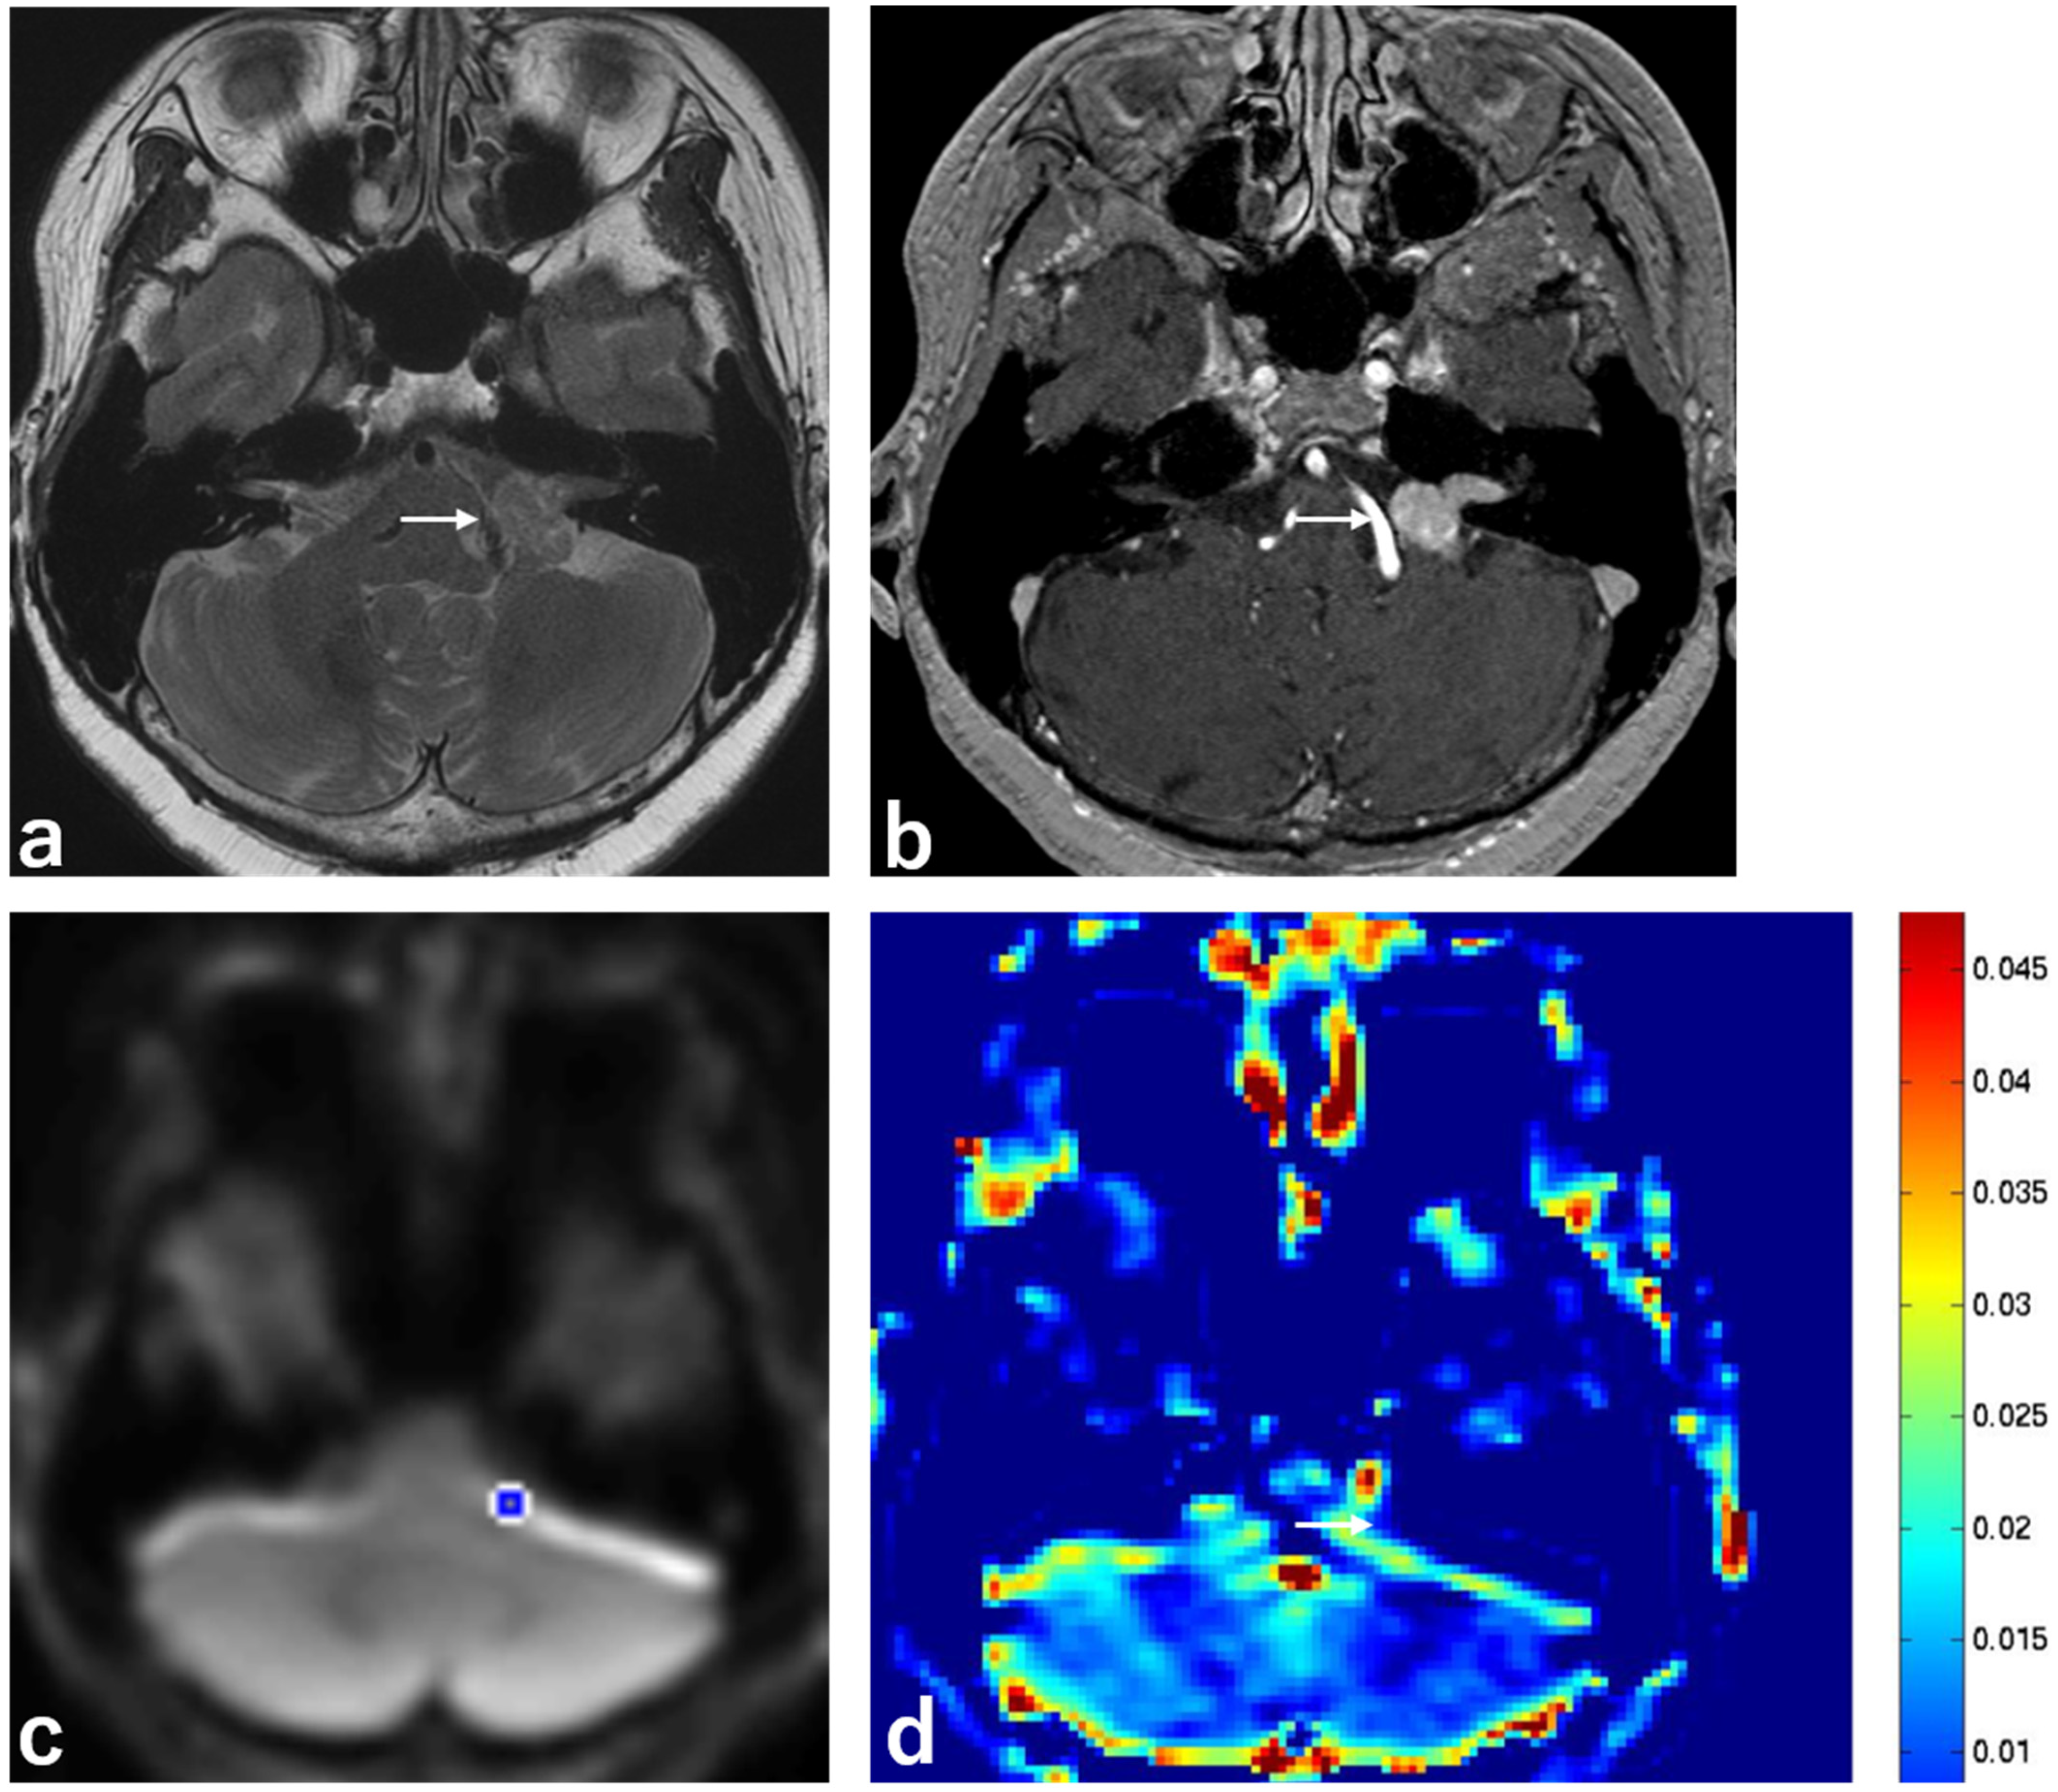

| Mean MTRasym | 0.033 ± 0.012 | 0.021 ± 0.004 | 0.007 |

| T2 hyperintensity | 6 (66.7%) | 2 (22.2%) | 0.058 |

| Heterogeneous enhancement | 6 (66.7%) | 2 (22.2%) | 0.058 |

| Dural tail sign | 0 (0%) | 6 (66.7%) | 0.003 |